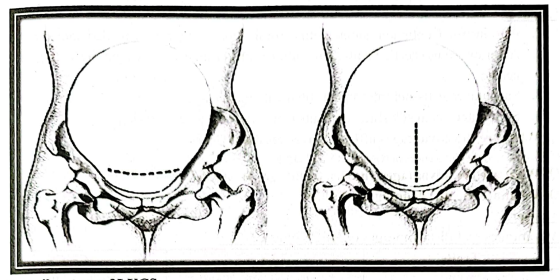

7. Incision: Pfennesteilineision is made commonly 3 cm above the pubic symphysis.

a. The loose peritoneum on the lower segment is cut transversely;

b. A short incision is made in the midline down to the membranes;

c. The incision of the lower segment is being enlarged using index finger of both hands.